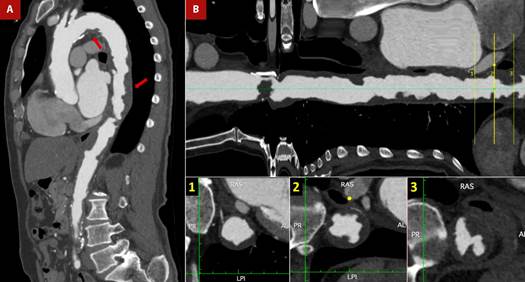

Figure 5 Shaggy aorta and thrombus. A 76-year-old man with a history of arterial hypertension, smoking, atrial flutter, and abdominal aortic aneurysm corrected by bilateral aorto-femoral bypass, referred intermittent claudication of the lower limbs. The patient was admitted on an outpatient basis for peripheral revascularization. The pre-surgical evaluation was complemented with transesophageal echocardiography (TEE) (see Figure 4) due to poor acoustic window in the transthoracic approach and a cardiac CT. A. CT angiogram - sagittal section of the aorta. Multiple atheromatous plaques, in tandem, along the entire course of the aortic arch and thoracoabdominal aorta (red arrows), predominantly in the supradiaphragmatic portion. B. Longitudinal reconstruction of the aorta. The cross-section shows plaques with a low attenuation coefficient (35 HU), irregular borders (lower central box), ulcerated and associated with images suggestive of thrombus (lower right box).